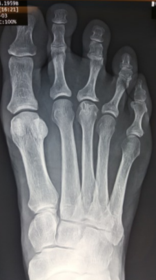

| What angle is this? Is this normal or abnormal? | 1st intermetatarsal angle Abnormal. Greater than 9 degrees is abnormal. Usually due to metatarsus primus varus |